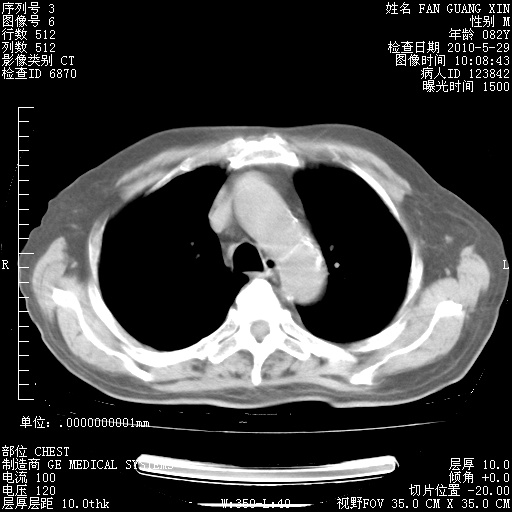

治疗3周后的肺部CT纵隔窗

再治疗10天后的肺部CT

再治疗10天后的肺部CT 纵膈窗